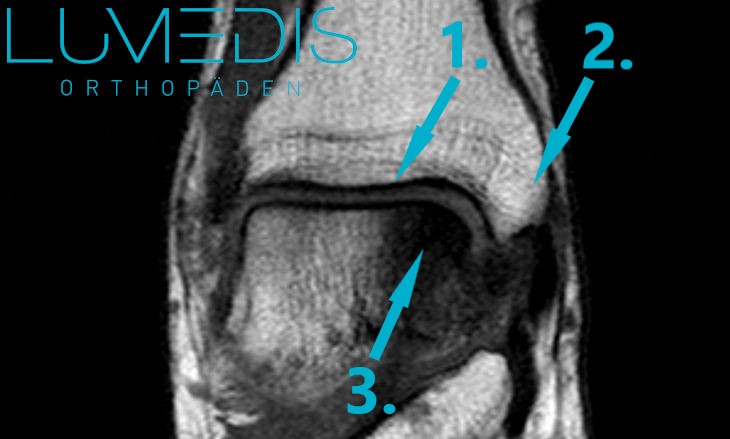

MRT einer Osteochondrosis dissecans (OD) medialer Talus

Röntgenbild eines Sprunggelenks mit einer Osteochondrosis dissecans (OD).

Der türkise Pfeil deutet auf die Osteochondrosis dissecans der medialen Talusrolle.

Hierbei handelt es sich um eine OD des Stadium IV.